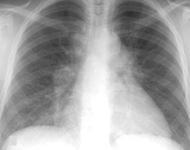

RT de asbestosis

De la colección personal de Kenneth D. Rosenman, Michigan State University